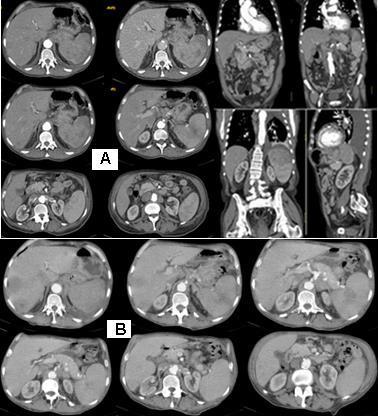

Abdominal CT

Figure 2: Abdominal CT with venous contrast, with axial transverse images and sagittal and coronal reconstructions: A/ А parenchymal mass lesion, originating in the stomach, with exophytic growth and incidental infiltrations, which has increased dimensions changed spotted hypodense structure, and pushes the left kidney medially and down. The formation structure is inhomogeneous, with a soft density, with the presence of hypodense areas centrally, possibly necrotic. Expressed lymphadenopathy paraaortal, around the stomach and the Celial Trunkus; B/ Abdominal CT with axial transverse images after 1 month with visible liver metastases and increased gastric formation with local infiltration in the spleen.

Abdominal CT with venous contrast, with axial transverse images and sagittal and coronal reconstructions: a parenchymal mass lesion, originating in the stomach, with exophytic growth and incidental infiltrations, which has increased dimensions changed spotted hypodense structure, and pushes the left kidney medially and down. The structure of the formation is inhomogeneous, with a soft density, with the presence of hypodense areas centrally, possibly necrotic. Expressed lymphadenopathy paraaortal, around the stomach and the truncus coeliacus (Figure 2/А). Abdominal CT scan after 1 month with visible liver metastases (Figure 2/В).